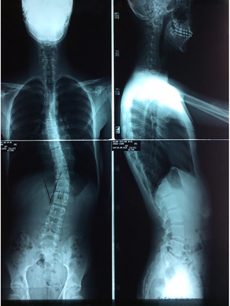

KORSE ÖNCESİ - SONRASI 1

korseler-1